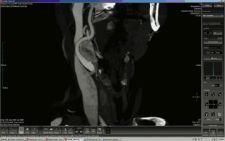

NovaPACS 6.6 by NovaRad offers embedded MIP (maximum intensity projection) and MPR (multiplanar reconstruction) tools to build and view 3D images directly from the PACS workstation.

The MIP and MPR tools included in NovaPACS reportedly eliminate the need for radiologists to perform post-processing reconstructions from the modalities and for technologists to redo reconstructions specified by the radiologists. Radiologists can reportedly reconstruct any study they want in any format they want right from NovaPACS.